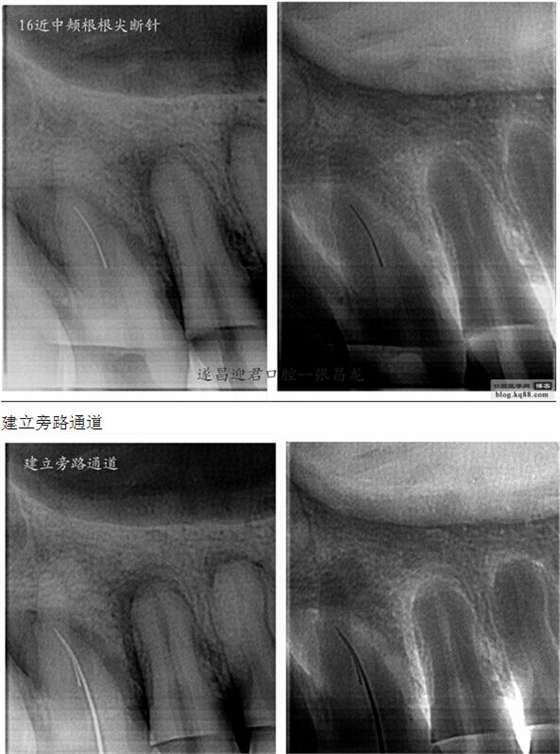

下面是我最近的一個(gè)患者,患者14,15,16均因楔狀缺損導(dǎo)致牙髓壞死,根管治療期間,16的近中頰根發(fā)生了斷針。

每個(gè)牙科醫(yī)生都不愿碰到器械分離,但常在河邊走,哪有不濕鞋的,我想大部分醫(yī)生根管治療中都發(fā)生過器械分離吧。在此就不在累贅那些造成根管器械分離的原因,醫(yī)生們也都知道那些。遇到器械分離莫慌,我們還是有挽救的余地。由于醫(yī)生的技術(shù)原因,設(shè)備原因,不是每個(gè)斷針都能取出來的。與對(duì)一部分?jǐn)噌樜覀兛梢試L試建立旁路通道,斷針與根管壁之間的間隙慢慢通入到工作長度,然后常規(guī)根管治療。